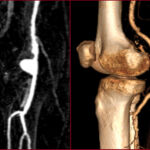

Περιφερική αγγειοπάθεια

Η περιφερική αγγειοπάθεια είναι η νόσος κατά την οποία οι αρτηρίες που τροφοδοτούν τα άκρα στενεύουν ή αποφράσσονται, συνήθως λόγω αθηροσκλήρωσης, μειώνοντας τη ροή αίματος προς τους ιστούς.